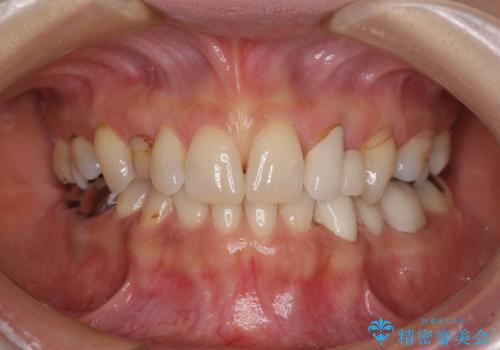

- 残存している乳歯や欠損部の隙間を気にして来院された患者様です。

隙間が全て閉じたことで、長年食事の度に挟まる不快感が改善されました。

また、正面から見た印象がまるで自分の歯であるような自然な仕上がりとなりました。